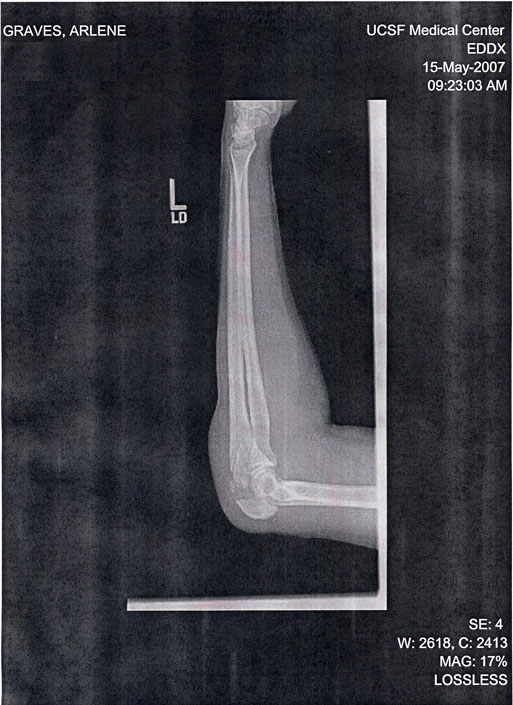

Ulna in several pieces (see left). Praise for stoicism. IV. Pain killers. First ever adult overnight hospital stay. Surgery on Wednesday: plate + 8 screws. 2nd night at hospital. Veg hospital food pretty good. :-) Great caregivers. Came home Thursday - missed all BTWD fun :-(. Recovering. Rest, ice, elevation, pain meds every 4 hours.

It's funny how easy it is to misplace a few weeks, or a month, of your life due to an unfriendly experience with gravity.My time is blurred from May 16th, and only came back into focus at the end of nearly three weeks. The 15th is sharp and clear: the fall; the trip to the hospital; the modern, empty waiting room; apologizing so politely for getting blood on the x-ray machine; waiting until the software glitch showed my caregivers the digital x-ray image, and then, finally, knowing they had seen it from the alarmed looks on their faces and offers of strong medications... Having my ulna described as "shattered..." Being ordered to stay; getting a plaster splint and the initials of the doctor who cast it written in my shoulder in marker; getting an intake interview (and being able to emphasize my vegetarianism); falling into a medicated sleep, and dreaming of the fall onto the streetcar tracks, over and over, as vividly as the fall itself; being wheeled to "my" room when Steven was away, and worrying that he'd have trouble finding me; meeting my darling young doctors (attending doctors? Residents? my co-workers would have adored them), who told me I could have surgery at odd hours of the morning, OR when everyone is rested and awake (my choice!); learning from them that I'd receive a plate and 8 screws to reassemble my ulna, which was also cracked lengthwise; listening to construction noises echoing outside; being allowed to eat dinner once my surgery was postponed until morning; having Steven try to console me, and bring me things to read; being afraid to use 'the pain button,' but using it anyway, often; having to tow my IV into the bathroom with me, with assistance, on and off throughout the night...

The 17th. Having the night nurse introduce herself to me again (which I thought was funny for the brief period when I was lucid). Pain. Going to the bathroom 1,000 times, each time with assistance and several minutes of rolling-mechanical-island. Dreaming of biking along the Embarcadero without incident. Having the pain button fail. Having both night nurses working on my pain med dispenser at some ungodly hour of morning, and swap it out with another, switching all my IV stuff over. Dreaming of biking through the countryside on a pleasant day without incident. Listening to the pulse alarm going off over and over, because the sensor didn't stay taped to my finger. Being mildly annoyed by the breathing tube that gave me supplemental oxygen through my nose. Watching the sky get lighter through the blinds. Having the young doctors visit, and asking them to show me the x-ray: they brought in two, and each presented one to me, so I could FINALLY see what all the fuss was. Being relieved at Steven's return! Having the IVs removed. Getting dressed. Sitting in a wheelchair. Getting into the car. Having Steven drop me off at home with my modestly-sized cast while he got the prescriptions for vicodin and a stool softener (oh no). Having my parents visit briefly, and managing to stay awake for their visit.